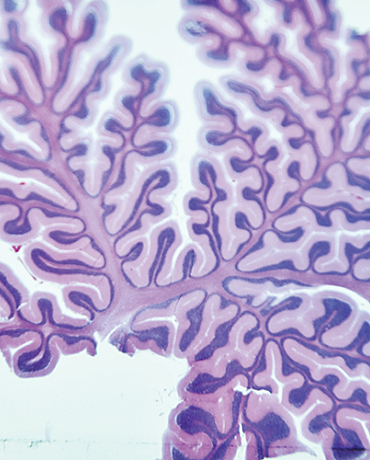

NeuRA is protecting and supporting brain health at every stage of life and working to prevent loss of function wherever possible.

We are advancing discovery and translational research into neurological conditions, prioritising early intervention, personalised care, and improved quality of life from pre-birth through to healthy ageing. We are working with our partners to introduce preventative strategies at the earliest possible time.